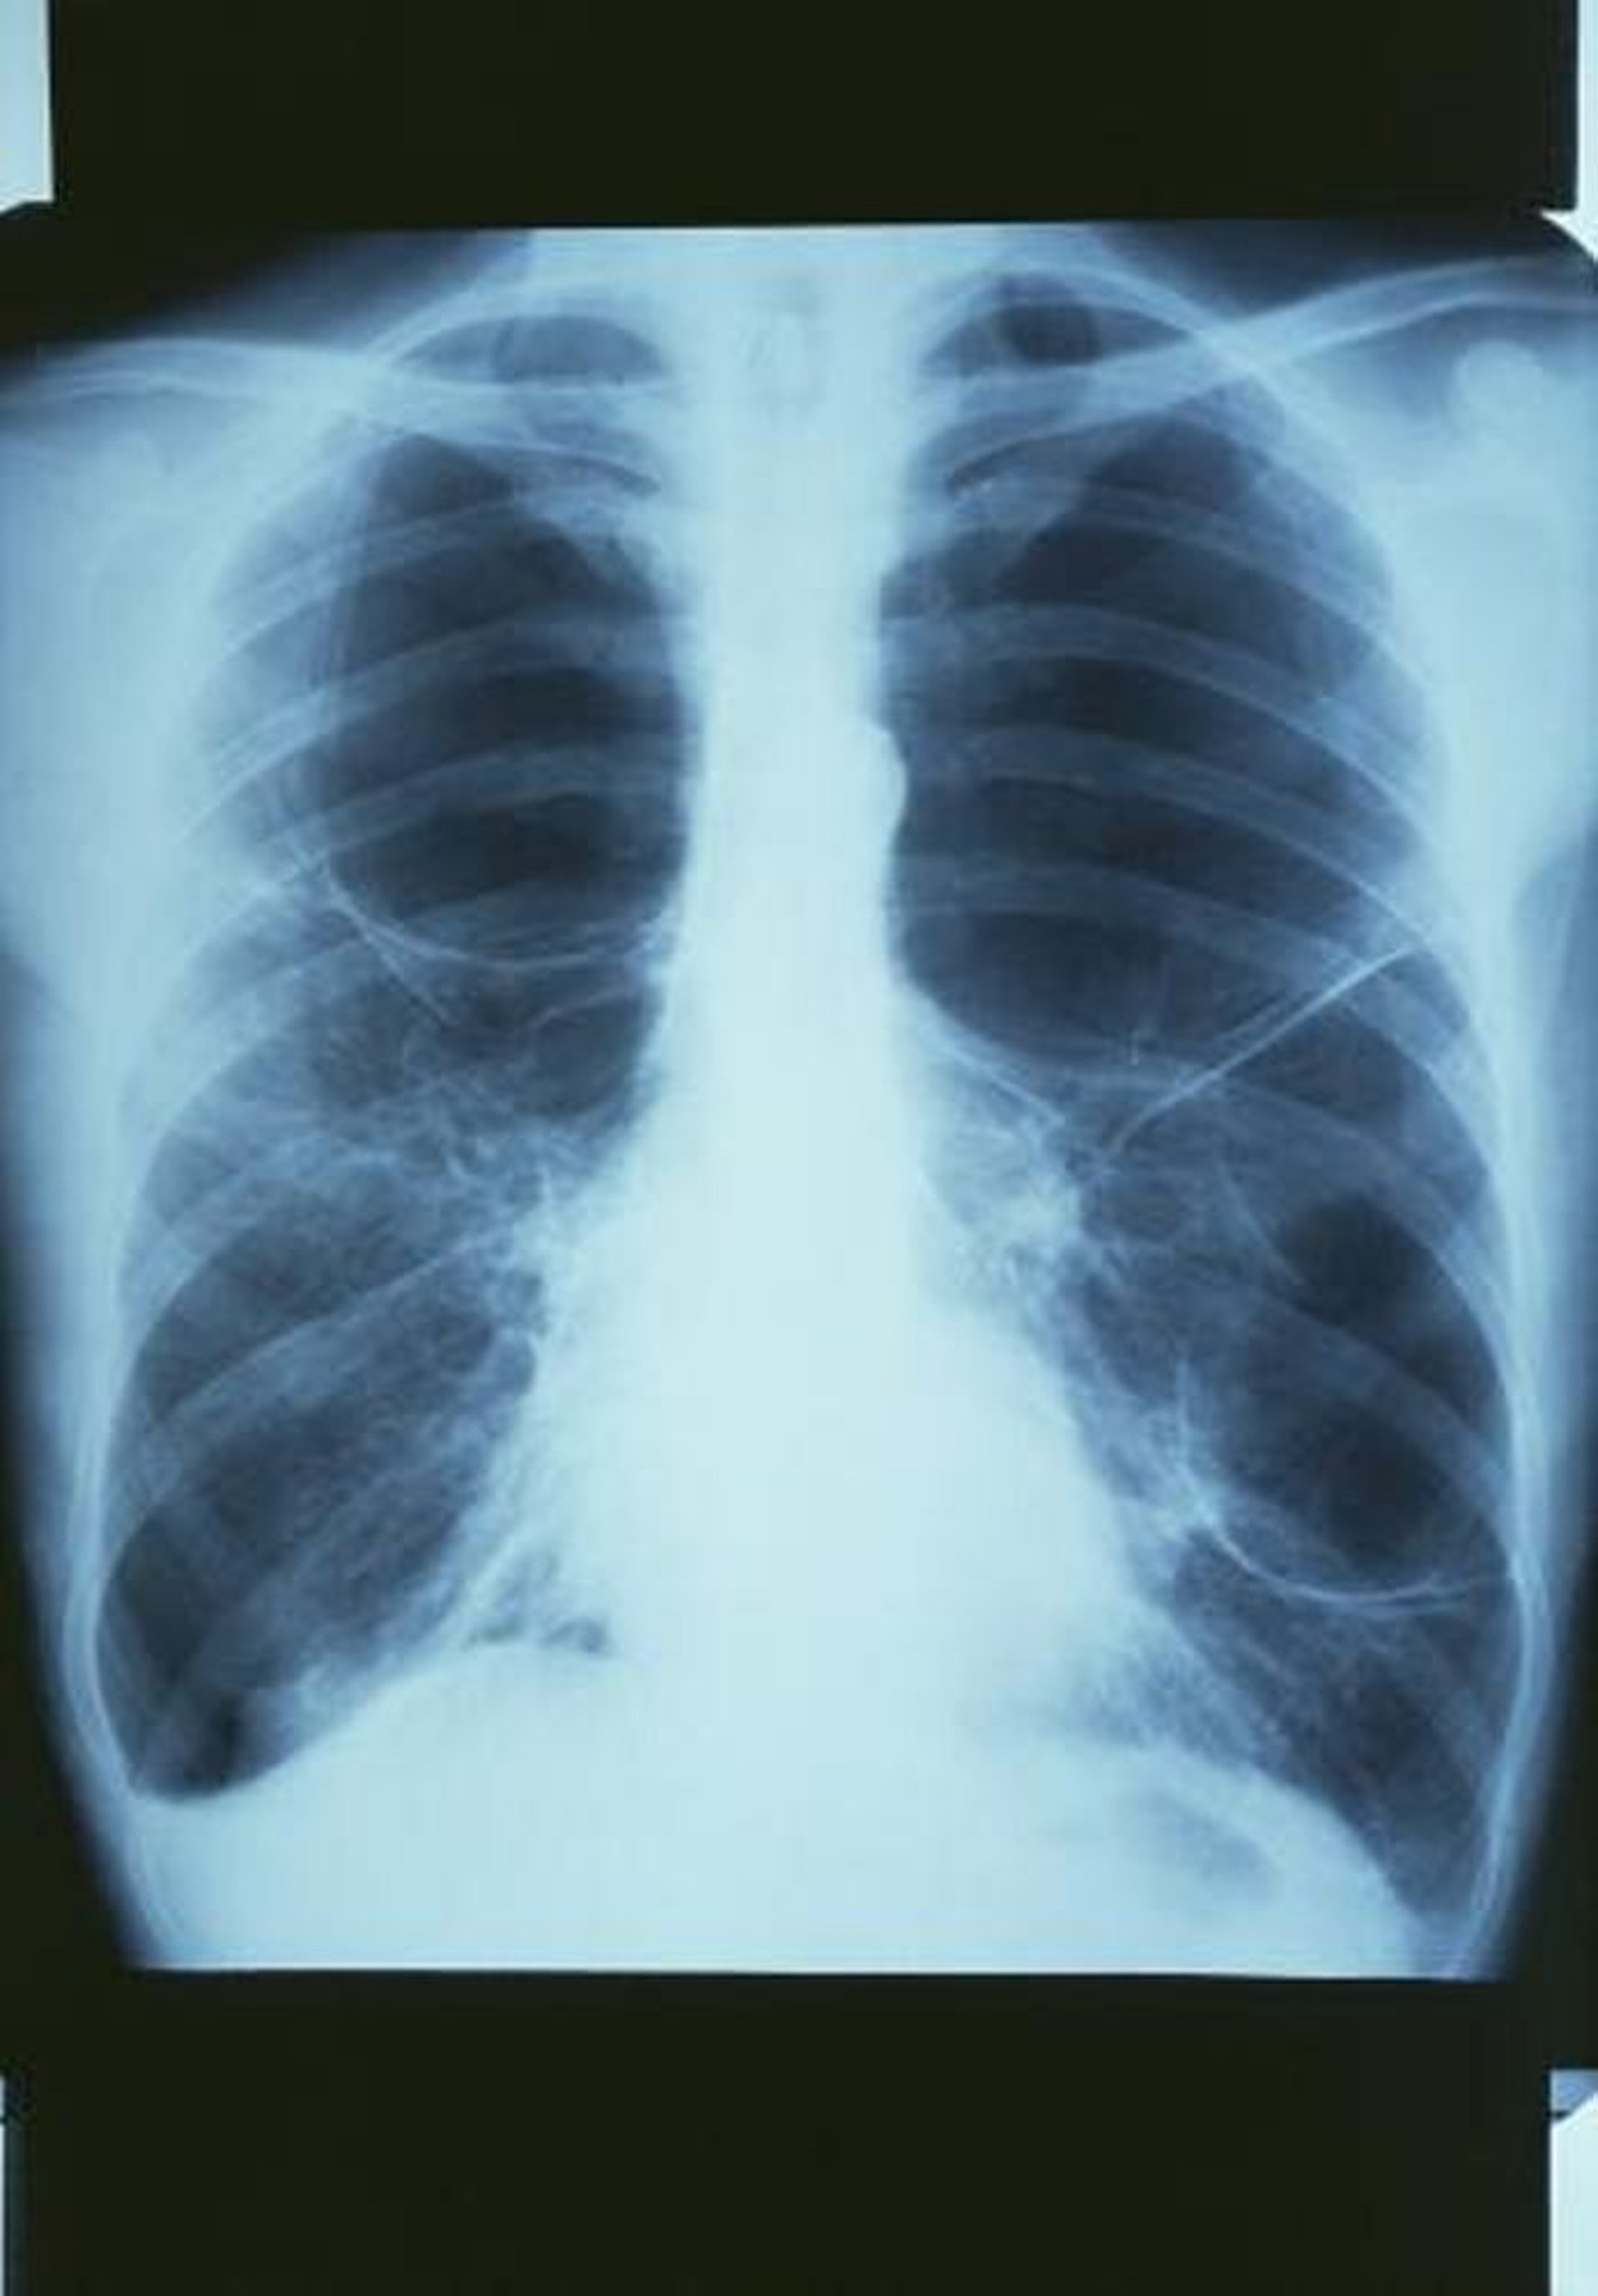

Enfermedad pulmonar obstructiva crónica con bullas

Esta radiografía de tórax muestra una ampolla grande en el pulmón superior derecho y 2 ampollas grandes en el pulmón izquierdo.

GJLP/CNRI/SCIENCE PHOTO LIBRARY